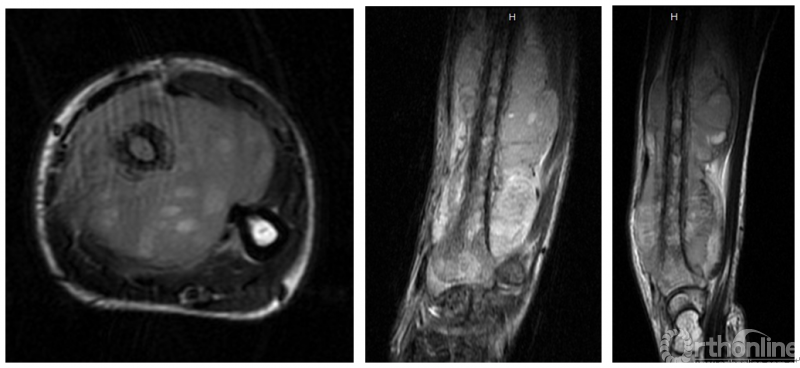

图7 右手背肿物手术送检标本图8 手术后右手背肿物病理图片尤因肉瘤

图片尺寸475x315